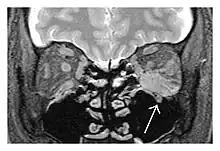

The extent of inflammation that can occur in IgG4-ROD is well demonstrated on magnetic resonance imaging (MRI).

![]() Enlargements in the left inferior rectus muscle and infraorbital nerve (arrow) in a 65-year-old man with a serum IgG4 of 404 mg/dL.[1] (T2-weighted MRI) |